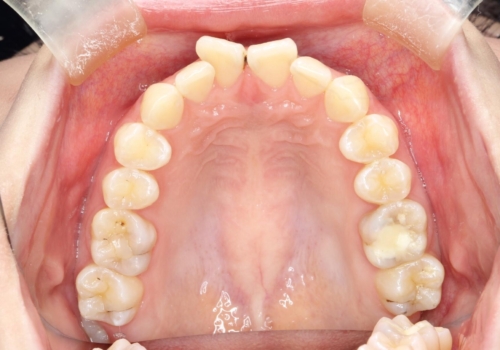

前歯のガタつきを治したい 翼状捻転マウスピース矯正

- 上顎前歯の突出、がたつき(翼状捻転)を主訴に来院されました。当院では総合歯科医療が可能であるため、矯正前処置として虫歯治療・歯周治療、親知らず抜歯を施行しました。その後、非抜歯かつ口元が出ないようなマウスピース治療を行いました。仕事柄、1日の装着時間が短くなってしまう時期もありましたが、患者様と相談しながら問題なく終了しています。